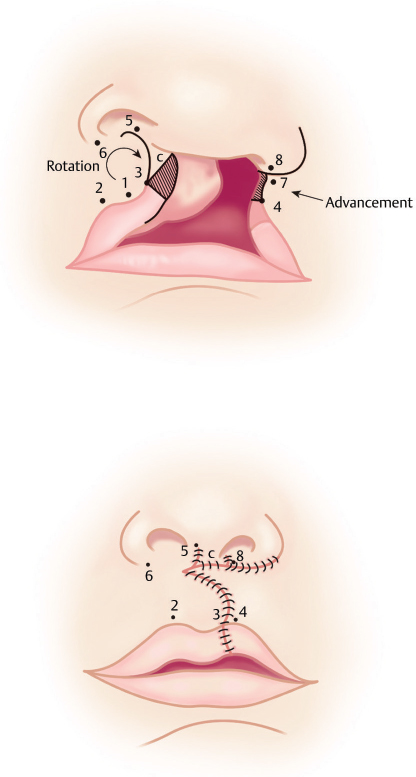

The drawing can be made in the following steps (Fig. 21.2):

• Step 1. Mark the bilateral commissures, Cupid’s bow peak on the noncleft side at the vermillion cutaneous border and its mirror image, along with its match on the lateral lip element. The base of the nostrils on the medial and lateral edge, the subnasale, and the midpoint of the Cupid’s bow are also marked.

• Step 2. Once the landmarks have been marked, draw the rotation flap on the medial lip element. This is drawn from the mirror image of Cupid’s bow peak arching toward the midpoint of the columella, and then making a sharp downward turn at the midpoint of the columella.

• Step 3. The advancement flap is on the lateral lip element by drawing a line from Cupid’s bow peak match, along the cleft, and turning at the nasal sill.

• Step 4. The columellar flap is then made from Cupid’s bow peak on the medial cleft element to the lateral columella.

• Step 5. The mucosal incisions are marked as extensions of the rotation and advancement flaps.